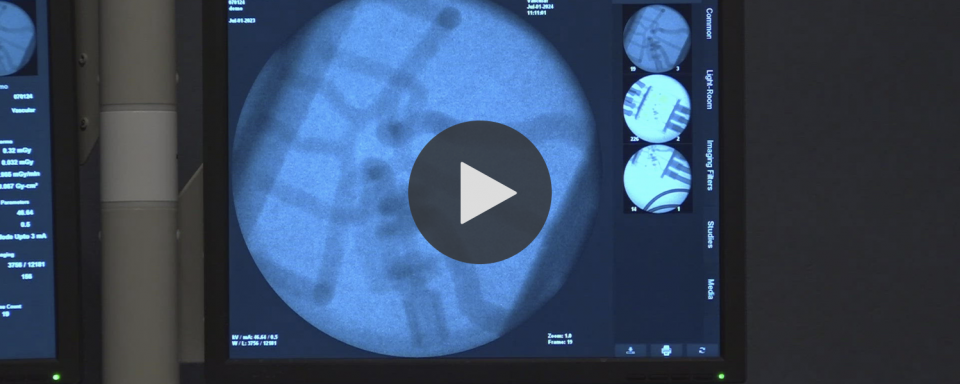

- 12 News video – August 16, 2024